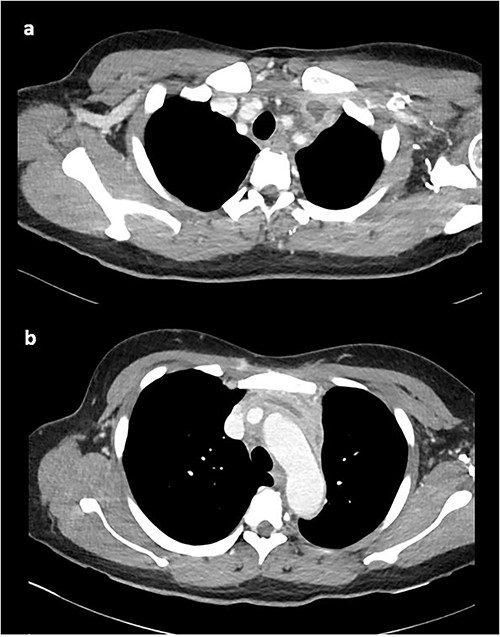

A computed tomography pulmonary angiogram (CTPA) was performed in the Emergency Department. Marked cresenteric aortic thickening from the level of the origin of the brachiocephalic trunk to the aortic hiatus in the diaphragm was noted, seen in Fig. 1. The CTPA was subsequently reported as an acute aortic intramural haematoma. The patient was transferred to the intensive care unit for blood pressure control with intravenous labetalol and cardiac monitoring.

On repeat review of the CTPA, imaging was deemed atypical for acute aortic syndrome. A CT aortogram with delayed phase was performed, which demonstrated a 66-mm upper anterior mediastinal soft tissue density compressing the left brachiocephalic vein, as seen in Fig. 2.

CT chest with contrast demonstrating anterior mediastinal soft tissue density in the (a) upper chest and (b) lower chest.